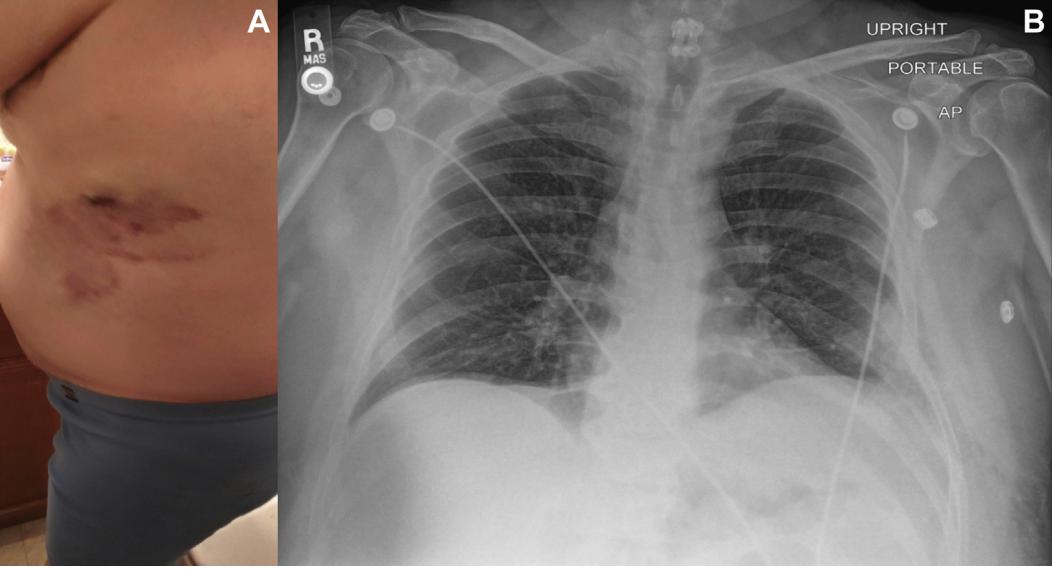

肺气肿x线,肺x线

肺气肿的影像诊断

肺气肿x线表现

肺气肿x线胸片特征

肺气肿的x线表现图片

肺气肿胸片典型图片